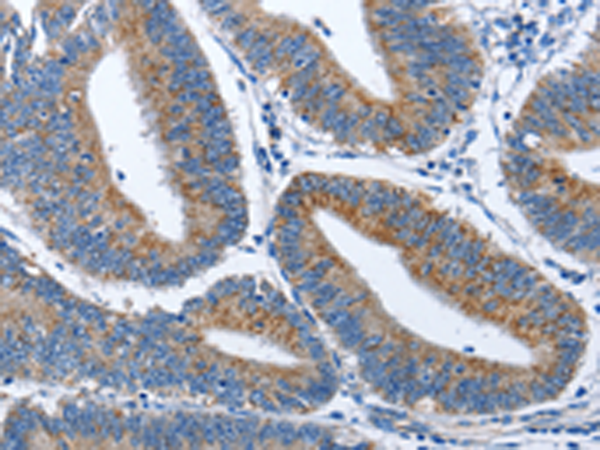

分类: 科研抗体货号: P08109别名: SPGF7; CATSPER应用: IHC反应种属: Human